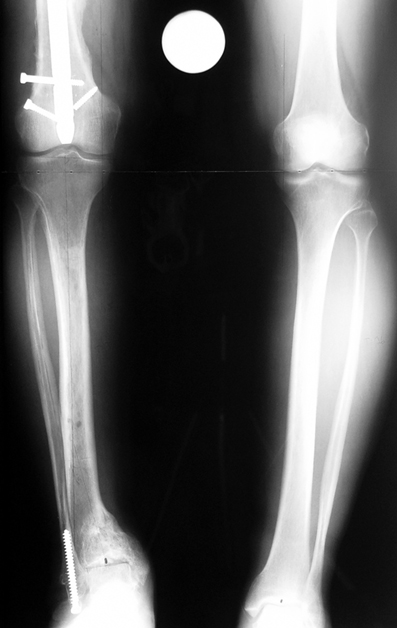

Vaka 3